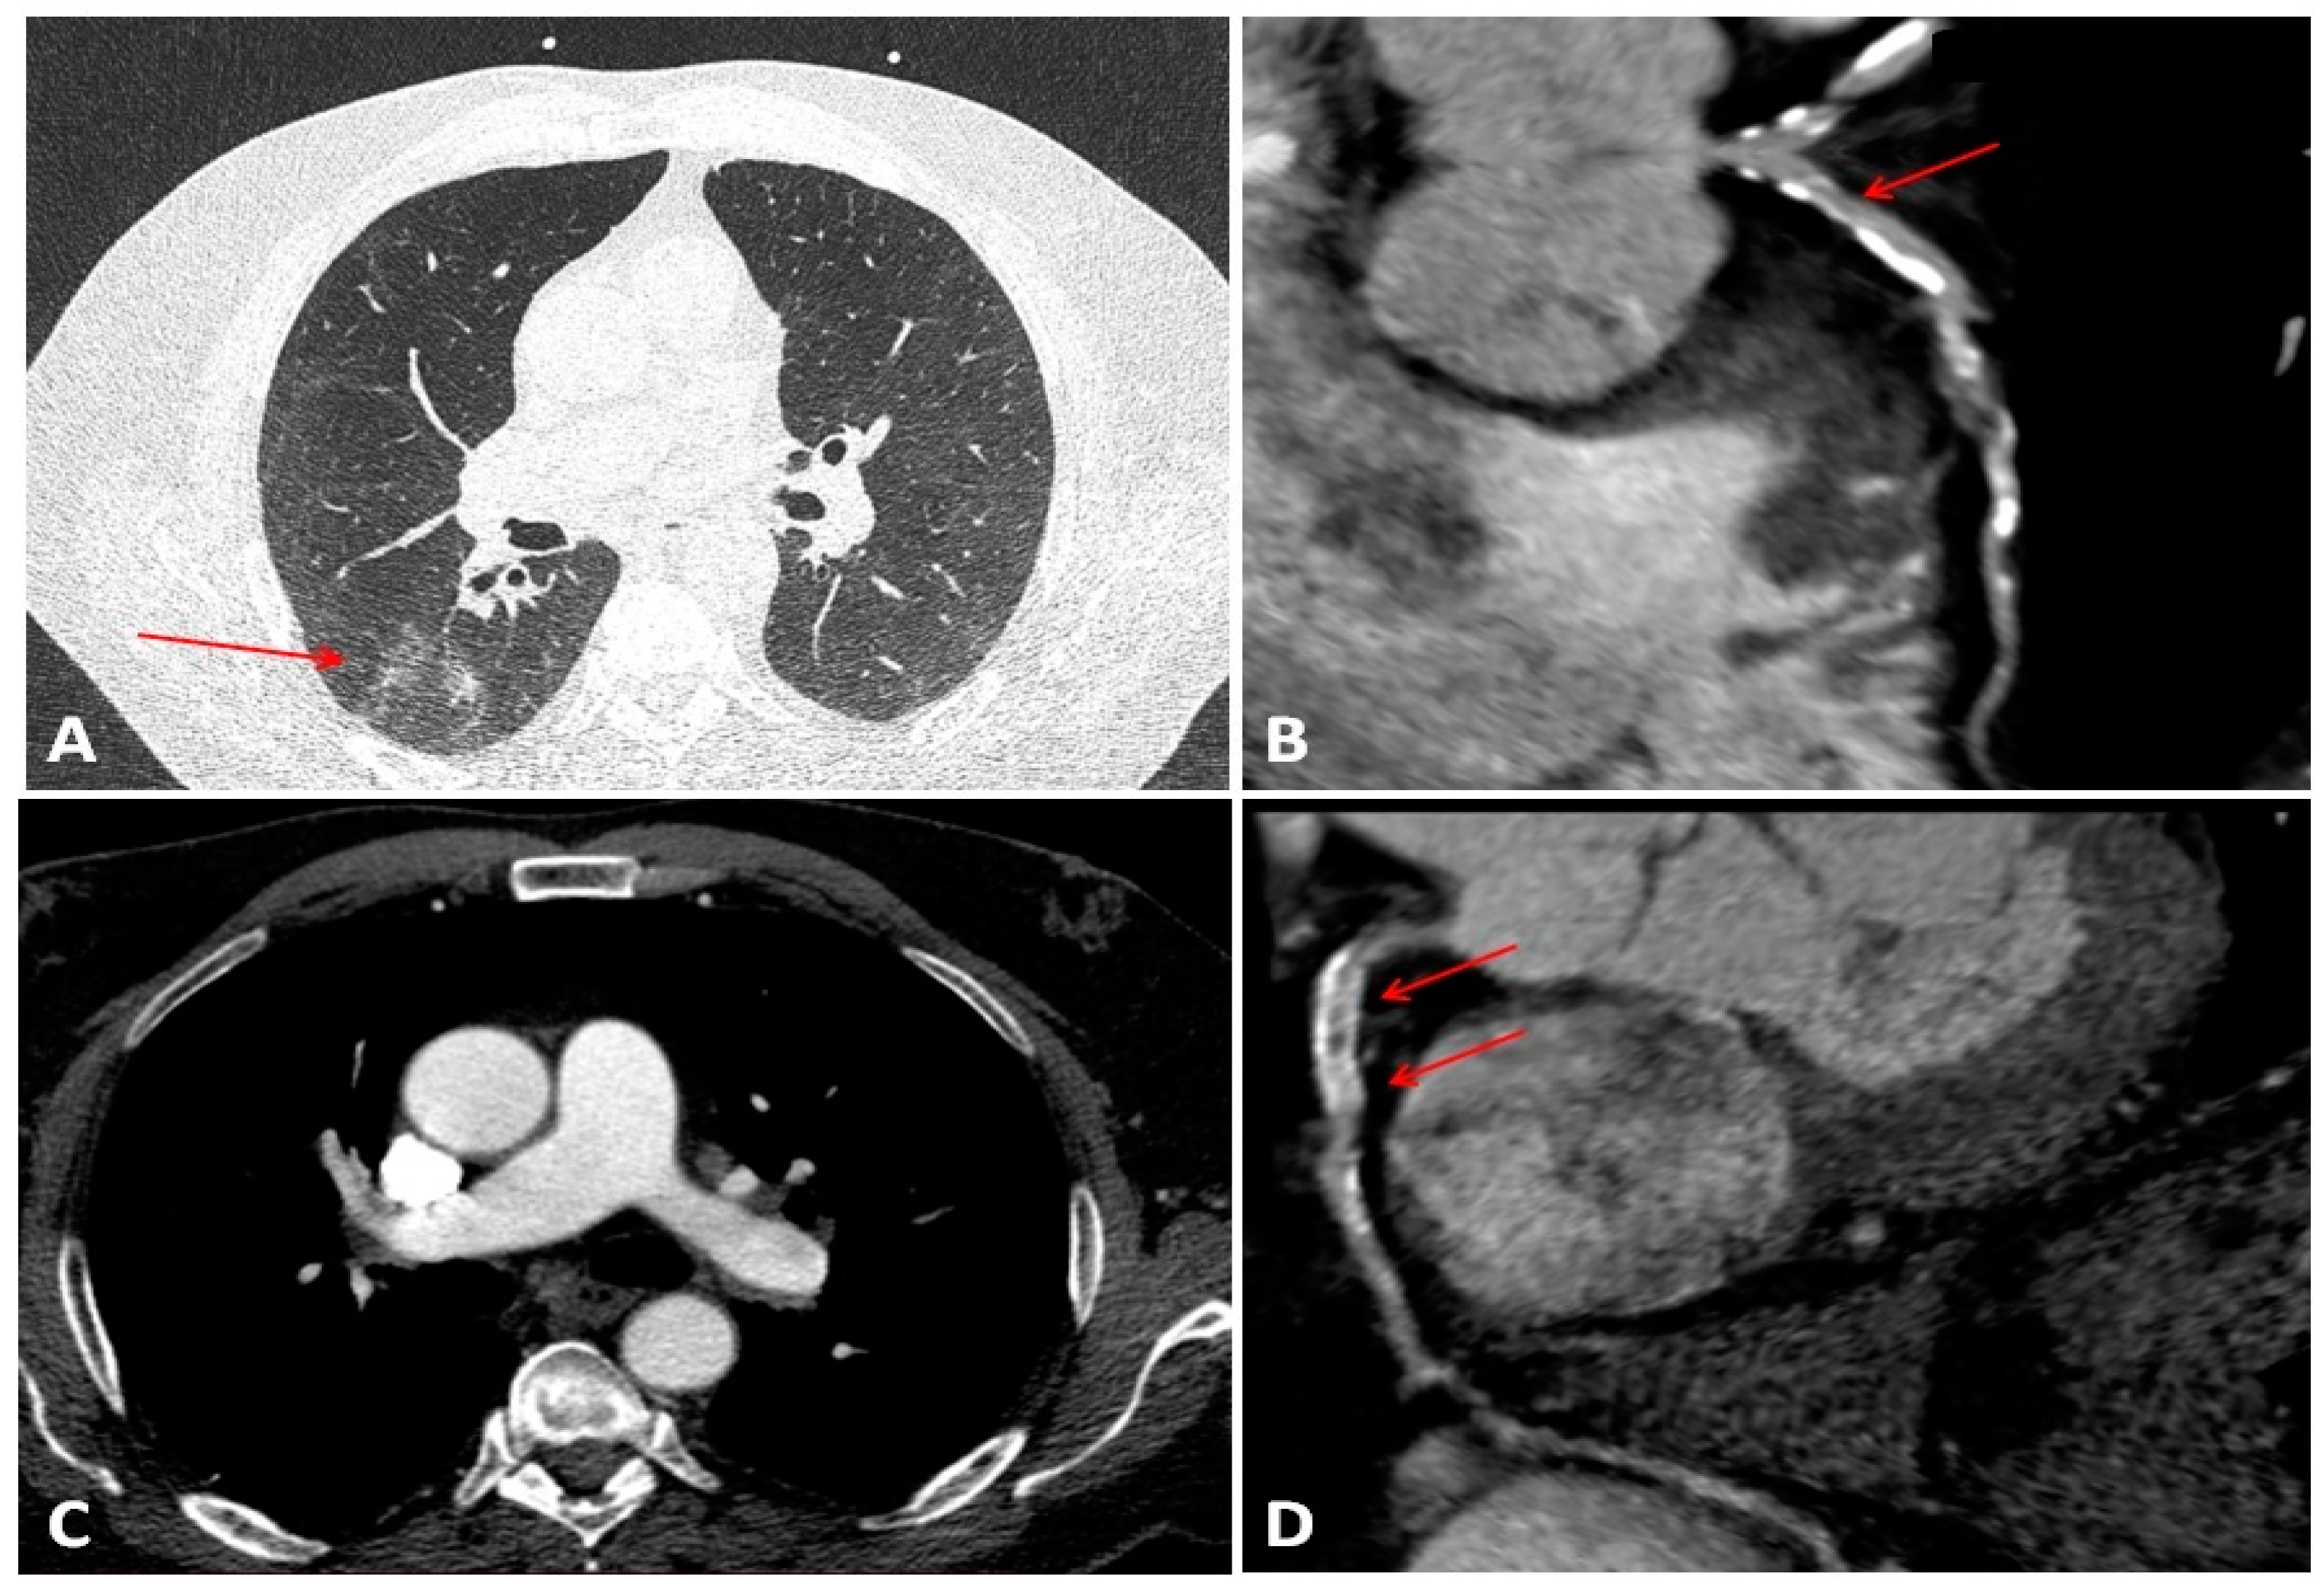

- Pontone, G.; Baggiano, A.; Conte, E.; Teruzzi, G.; Cosentino, N.; Campodonico, J.; Rabbat, M.G.; Assanelli, E.; Palmisano, A.; Esposito, A.; et al. “Quadruple Rule-Out” With Computed Tomography in a COVID-19 Patient With Equivocal Acute Coronary Syndrome Presentation. JACC Cardiovasc. Imaging 2020, 13, 1854–1856. [Google Scholar] [CrossRef] [PubMed]